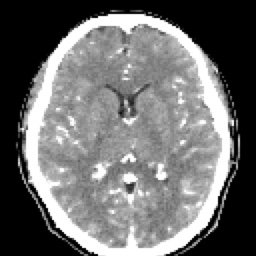

SIMPLE FINO (4) 129 images

ARTERIAL FINO (7) 129 images